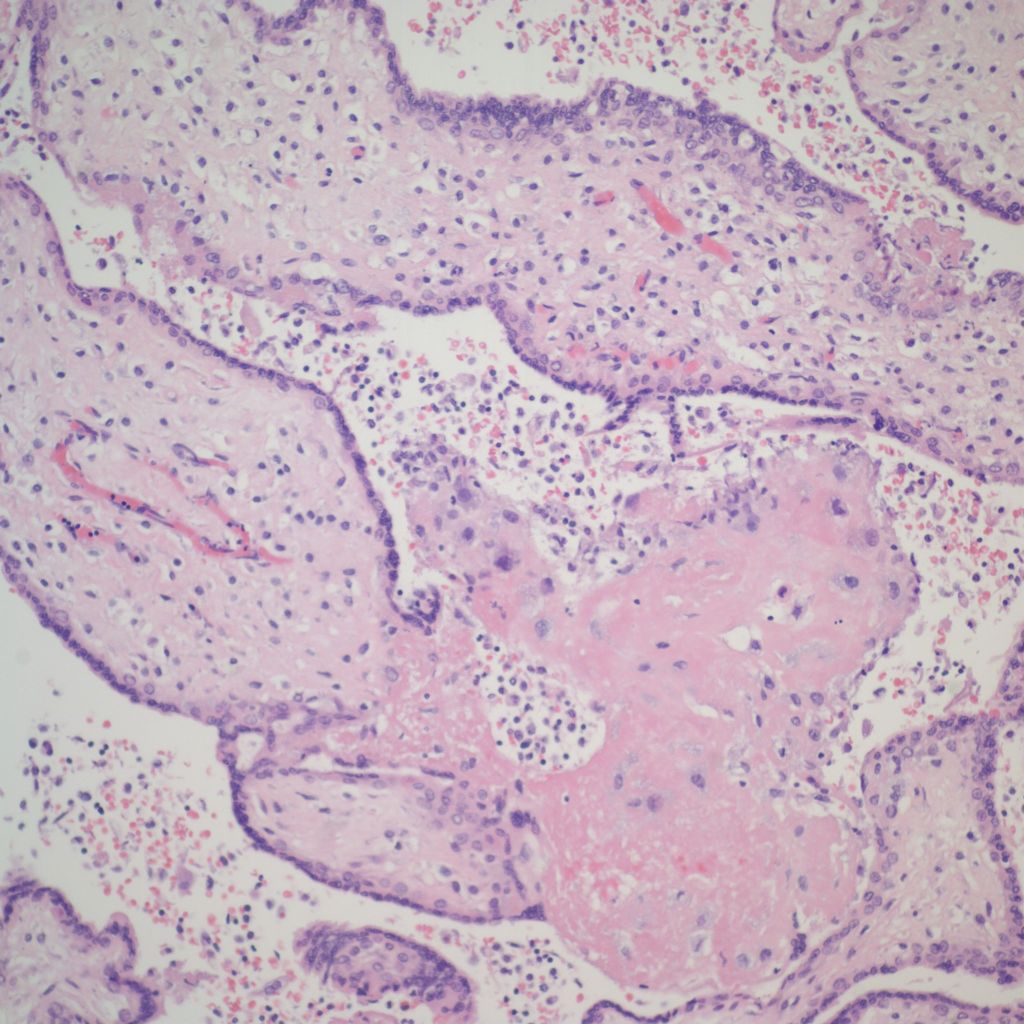

High Grade (massive) CHIV

Low Grade CHIV (5-50% of the intervillous space occupied by monocytes)

There is a focus of intervillous fibrinoid with no definite cytotrophoblast that is not re-covered with syncytium suggestive of recent syncytial injury (F). (10x, H&E)